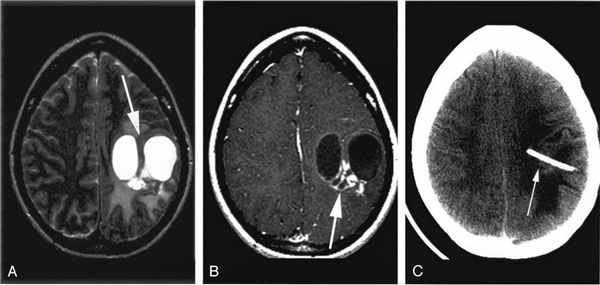

Наиболее важная дифференциация заключается между арахноидными кистами и эпидермоидными кистами; МРТ (DWI) облегчают дифференцировку этих нозологий. Некоторые арахноидные кисты содержат белковые жидкости или кровь; в таких случаях потеря сигнала на DWI может не маркироваться, что может представлять проблемы диагностики. Кроме того, контраст ткани с визуализацией с восстановлением обратной связи с флуоресценцией (FLAIR) аналогичен изображению с T2-взвешенным изображением, но FLAIR не показывает сигнал, возникающий из CSF. Таким образом, в отличие от эпидермоидных кист, арахноидальные кисты, содержащие CSF, демонстрируют подавленный (низкий) сигнал на FLAIR.

На изображениях они визуализируются в виде четко отграниченной полости с невидимыми стенками, оттесняющей прилегающие структуры, с сосдержимым характеризующимся паттерном аналогичным паттерну церебросиннальной жидкости (гиподенсивный при компьютерной томографии, гиперинтенсивный на Т2 взвешенных изображениях и гипоинтенсивный на Т1ВИ при магнитно-резонансной томографии). Они так же могу вызывать ремоделирование прилегающей кости.

Арахноидальные кисты на МРТ